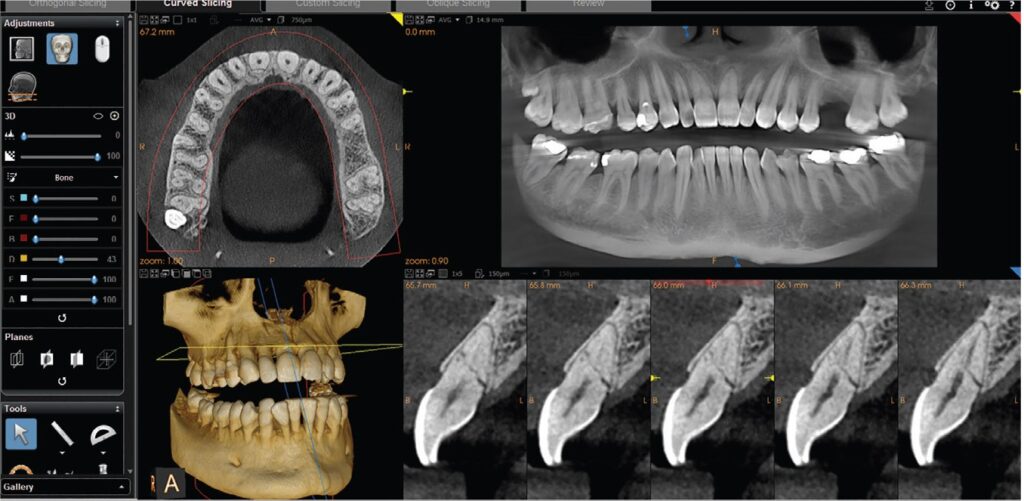

🌿 Cone Beam CT (CBCT) Scanning

Our 3D Cone Beam CT scanner provides high-resolution, cross-sectional images of your teeth, jawbone, sinuses, and surrounding structures. This allows us to:

• Plan complex procedures like implants and extractions with pinpoint accuracy

• Detect hidden infections, cysts, or bone loss

• Evaluate airway and sinus anatomy for sleep apnea and other conditions

Unlike traditional CT scans, CBCT uses a lower dose of radiation and delivers faster results—right from our office.